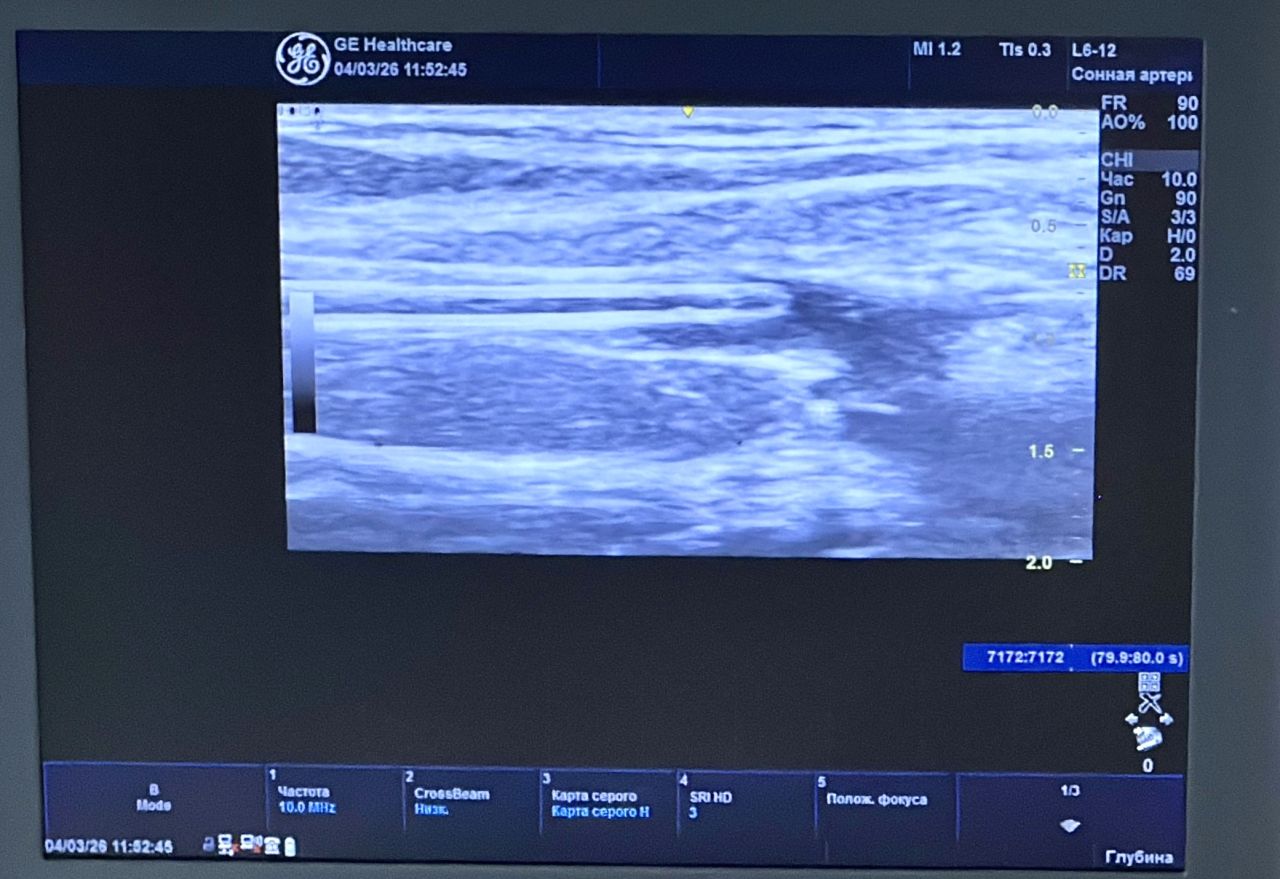

В клинике Рязанского государственного медицинского университета имени академика И.П. Павлова впервые выполнена процедура клеевой облитерации подкожных вен с использованием современной системы VenaSeal.

Метод применяется для лечения варикозной болезни и относится к числу наиболее щадящих малоинвазивных технологий. В ходе процедуры под ультразвуковым контролем в поражённую вену вводится специальный медицинский клей, который «запечатывает» сосуд и выводит его из патологического кровотока. Вмешательство выполняется через микропрокол и занимает всего несколько минут.